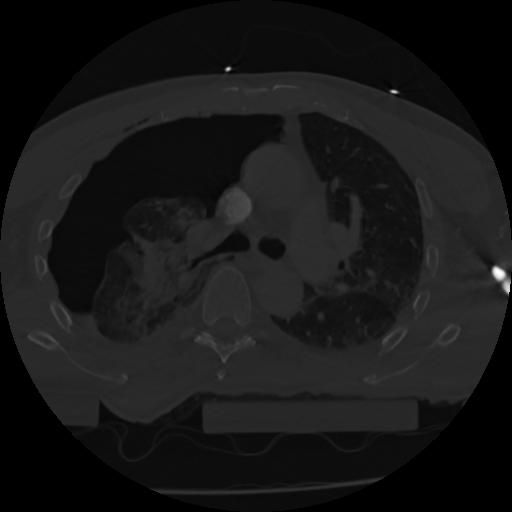

22 ANGIO,CE,Vol,0.5,ANGIO,,